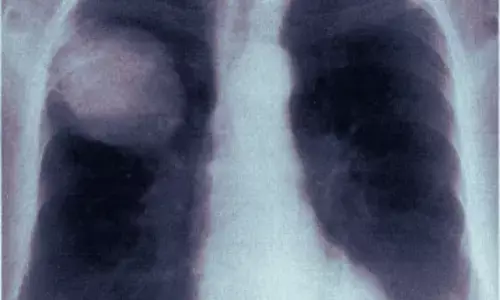

Study Reports First Successful Non-Surgical Treatment of Postoperative Lung Torsion

China: A recent case report published in BMC Surgery has documented the first successful conservative management of postoperative lung...